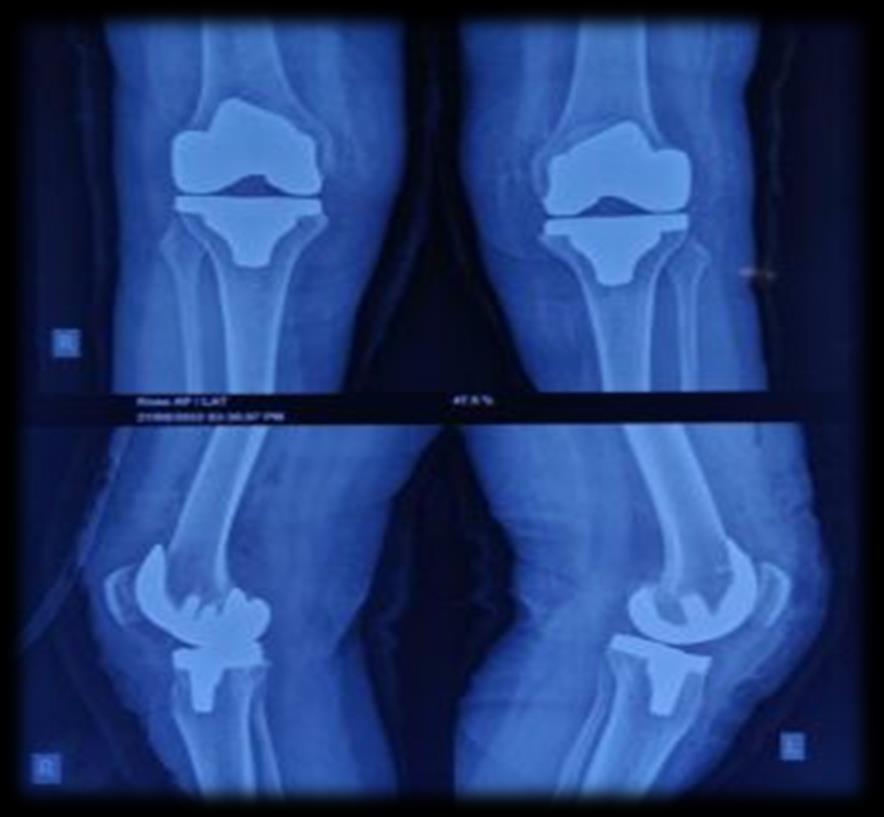

Two sides Knee Replacement

The bilateral procedures had a significantly higher rate of complications than unilateral procedures, almost entirely because of thromboembolic problems. The studies have shown Bilateral TKA had an increased risk for all complication when compared with unilateral TKA regardless of health status. A greater than fourfold increase for the second and third quartiles, and a greater than threefold increase for the fourth quartile (least healthy patients. Therefore, we recommend simultaneous bilateral knee arthroplasty only for patients in ASA classes 1 and 2.